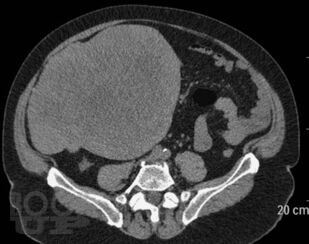

В книге приведены типичные клинико-рентгенологические ситуации, взятые авторами из повседневной практической работы в отделе лучевых методов диагностики и лечения Института хирургии им. А.В. Вишневского. Проанализированный материал охватывает хирургические заболевания органов брюшной полости и забрюшинного пространства вне острых или неотложных состояний. В первой части книги читателю предоставлена максимальная возможность сделать самостоятельное заключение о заболевании после анализа жалоб пациентов, анамнеза заболевания и приведенных изображений рентгеновских и КТ-исследований. Во второй части книги читатель может проверить правильность хода своих рассуждений и собственного заключения. Решение подобных ситуационных задач, несомненно, послужит большим подспорьем как начинающим, так и опытным врачам лучевой диагностики в их практической работе.